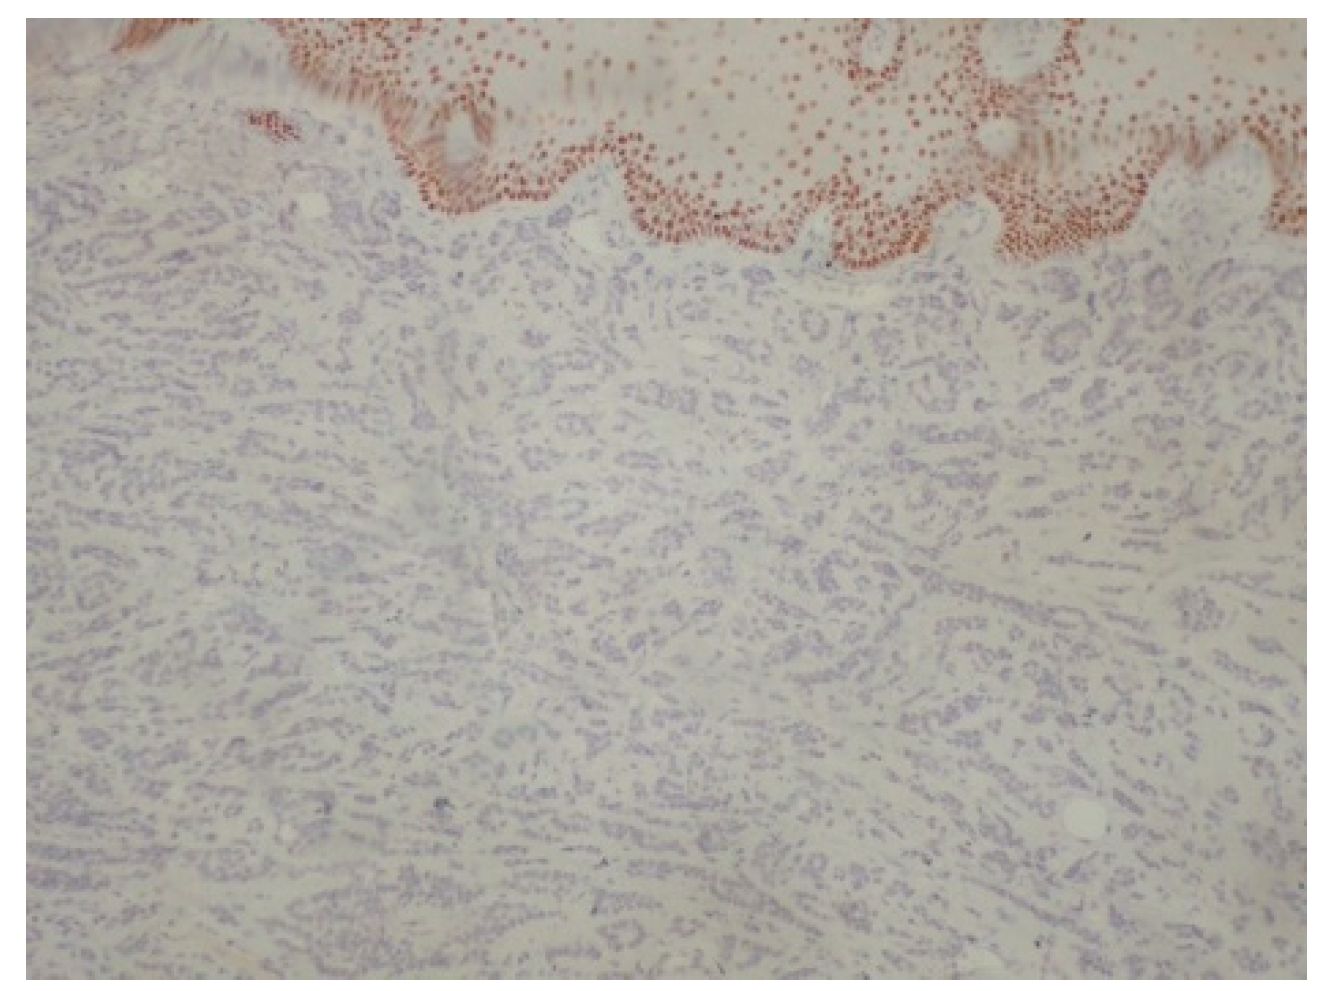

2. Case Presentation

3. Discussion